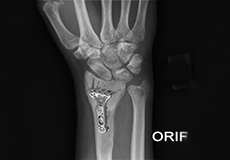

ORIF of Distal Radius Fracture

The forearm consists of two bones, the radius and ulna. The radius is the larger of the two forearm bones, and the region towards the wrist is called the distal end.

Wrist Open Reduction and Internal Fixation

Open reduction and internal fixation of the wrist is a surgical technique employed for the treatment of severe wrist fractures to restore normal anatomy and improve range of motion and function.